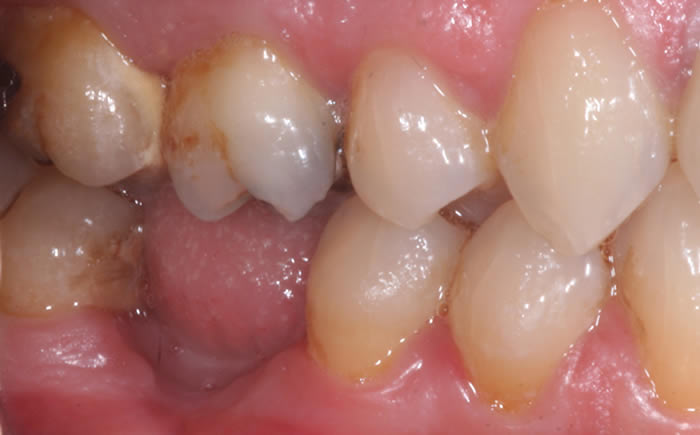

More back teeth replaced by dental implants

Case Five (4 images)